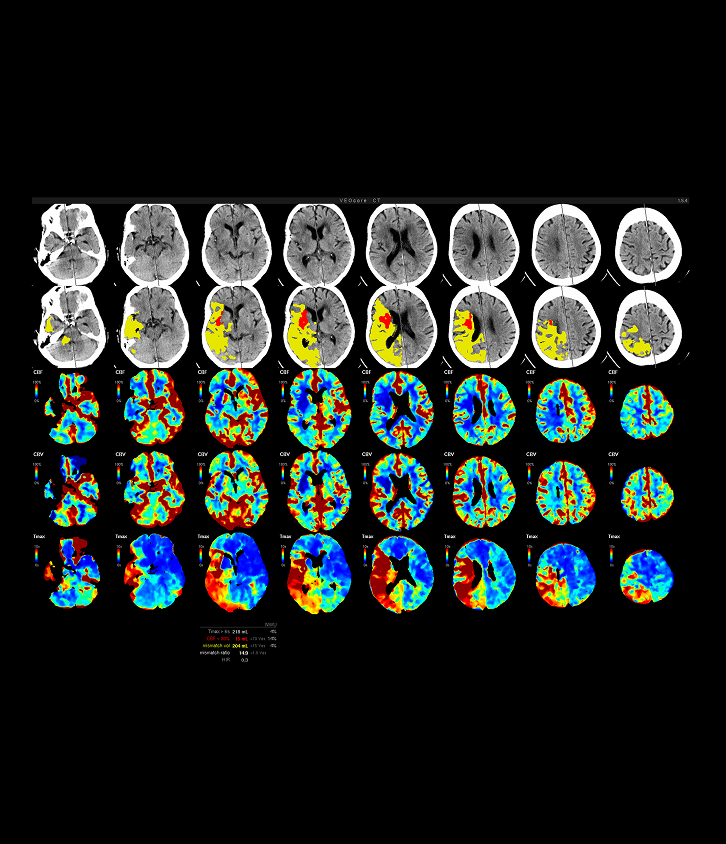

Der Schlaganfall erfordert schnelle, präzise Diagnostik und Entscheidungen – insbesondere im Hinblick auf die Thrombektomie. mRay VEO Core und mRay VEO Aspects unterstützen Sie mit automatisierten Perfusionsanalysen und ASPECTS-Scoring bei der Entscheidungsfindung, wenn jede Minute zählt.

• Leitlinienkonforme vollautomatische Auswertung von Perfusionsmessungen innerhalb von 3 Minuten.

• Anzeige der DEFUSE-3 Einschlusskriterien wie in der ESO Guideline [01.2019] vorgeschlagen:

infarct core volume, penumbra volume, mismatch ratio

• Intuitive Darstellung in einer 3D Übersicht: Infarktkern (rot) und Hypoperfusion (gelb) als farbiges Overlay, Darstellung von CBF und Tmax

• Quantitative Ergebnisse für die Güte der automatischen Auswertung: Warnung bei detektierter Patientenbewegung oder fehlerhafter Kontrastmittelinjektion.

ki basierte perfusionsanlyse screenshot mray veocore

Vollwertiger 3D Datensatz mit Hypoperfusion (TMAX>6s)

CBF/Mismatch mit MT Indication mRay VEOcore

mRay VEO Core: CBF/Mismatch mit MT Indikation

mRay VEO Core Lesion Map Mosaic: Übersicht der Perfusionsbildgebung